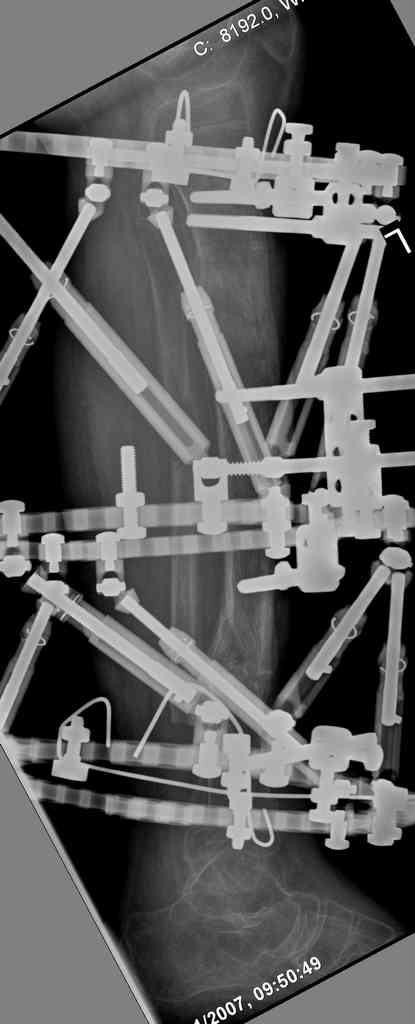

Another choice is simply perform shortening + posterior angulation with Ilizarov or TSF , than gradual correction of the angulation.After all apply third ring on the proximal tibia and start lengthening.

Another advantage of this techniqe is relaxation of soft tissue and possibility for closure even large defects of the skin.In your case I will apply ring on the foot and mid diaphysis of the tibia ,removal of the fibular plate,sindesmotic wire, and after correction of angulation on the proximal tibia.

> will apply ring on the foot and mid diaphysis of the tibia ,removal of

> the fibular plate,sindesmotic wire, and after correction of angulation

Да, надо удалить все железо, сделать для ангуляции остеотомию малоберцовой на уровне дефеормации, а после восстановления оси сразу освободить стопу. То есть в дистальном отломке tibia надо побольше

спиц с упорами, а на диафизе только half-pins с передне-внутренней стороны, чтобы как можно меньше пострадала передняя группа мышц.